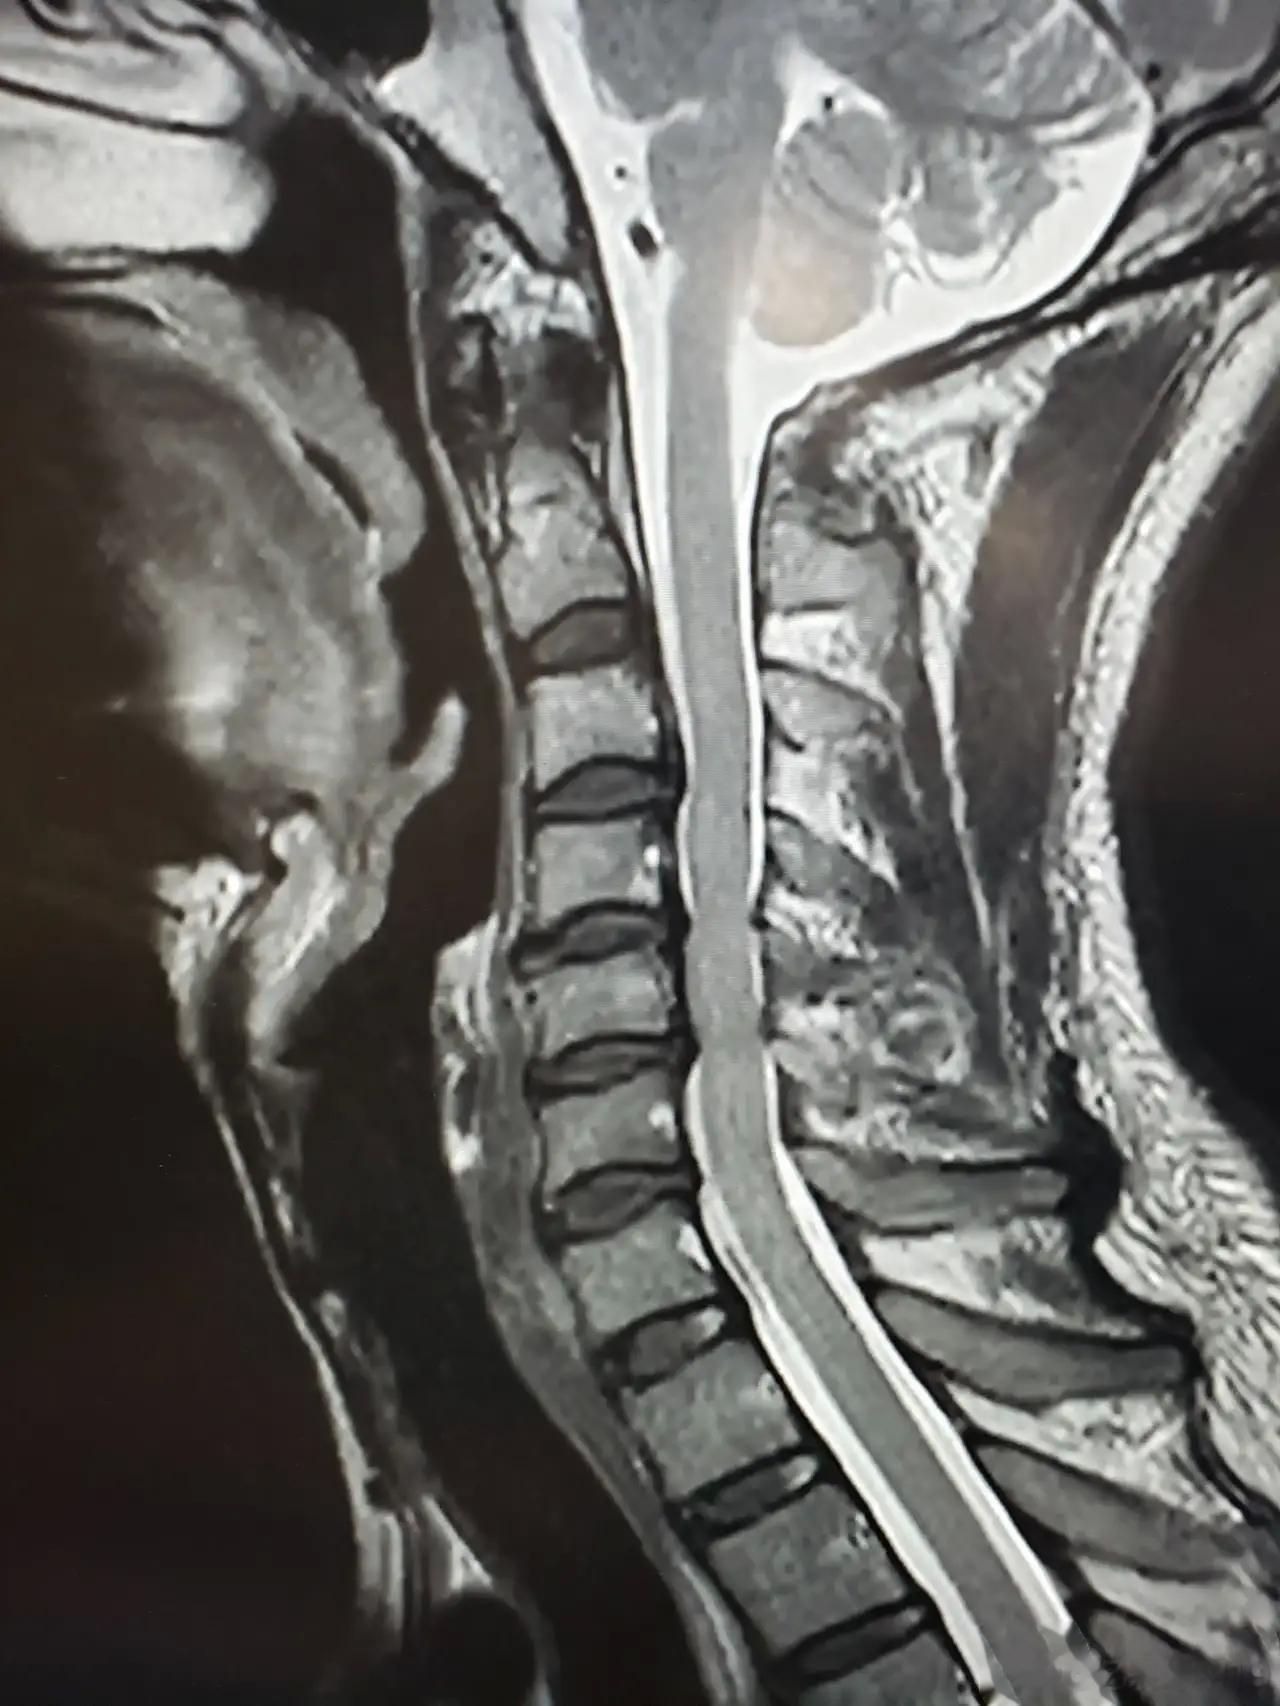

腰突出现4种情况,千万别硬扛着了1、腰椎局部的疼痛特别是在转腰、弯腰、扭腰的时候